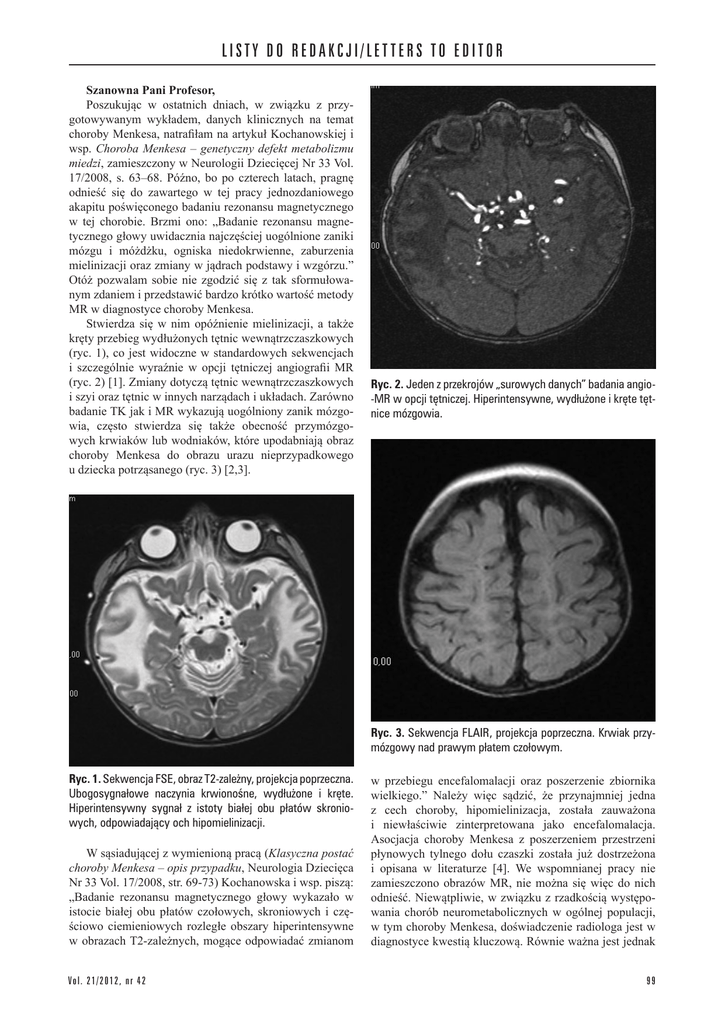

Ryc. 2. Jeden z przekrojów „surowych danych” badania angio-MR w opcji tętniczej. Hiperintensywne, wydłużone i kręte tętnice mózgowia.

(ryc. 2) [1]. Zmiany dotyczą tętnic wewnątrzczaszkowych

i szczególnie wyraźnie w opcji tętniczej angiografii MR